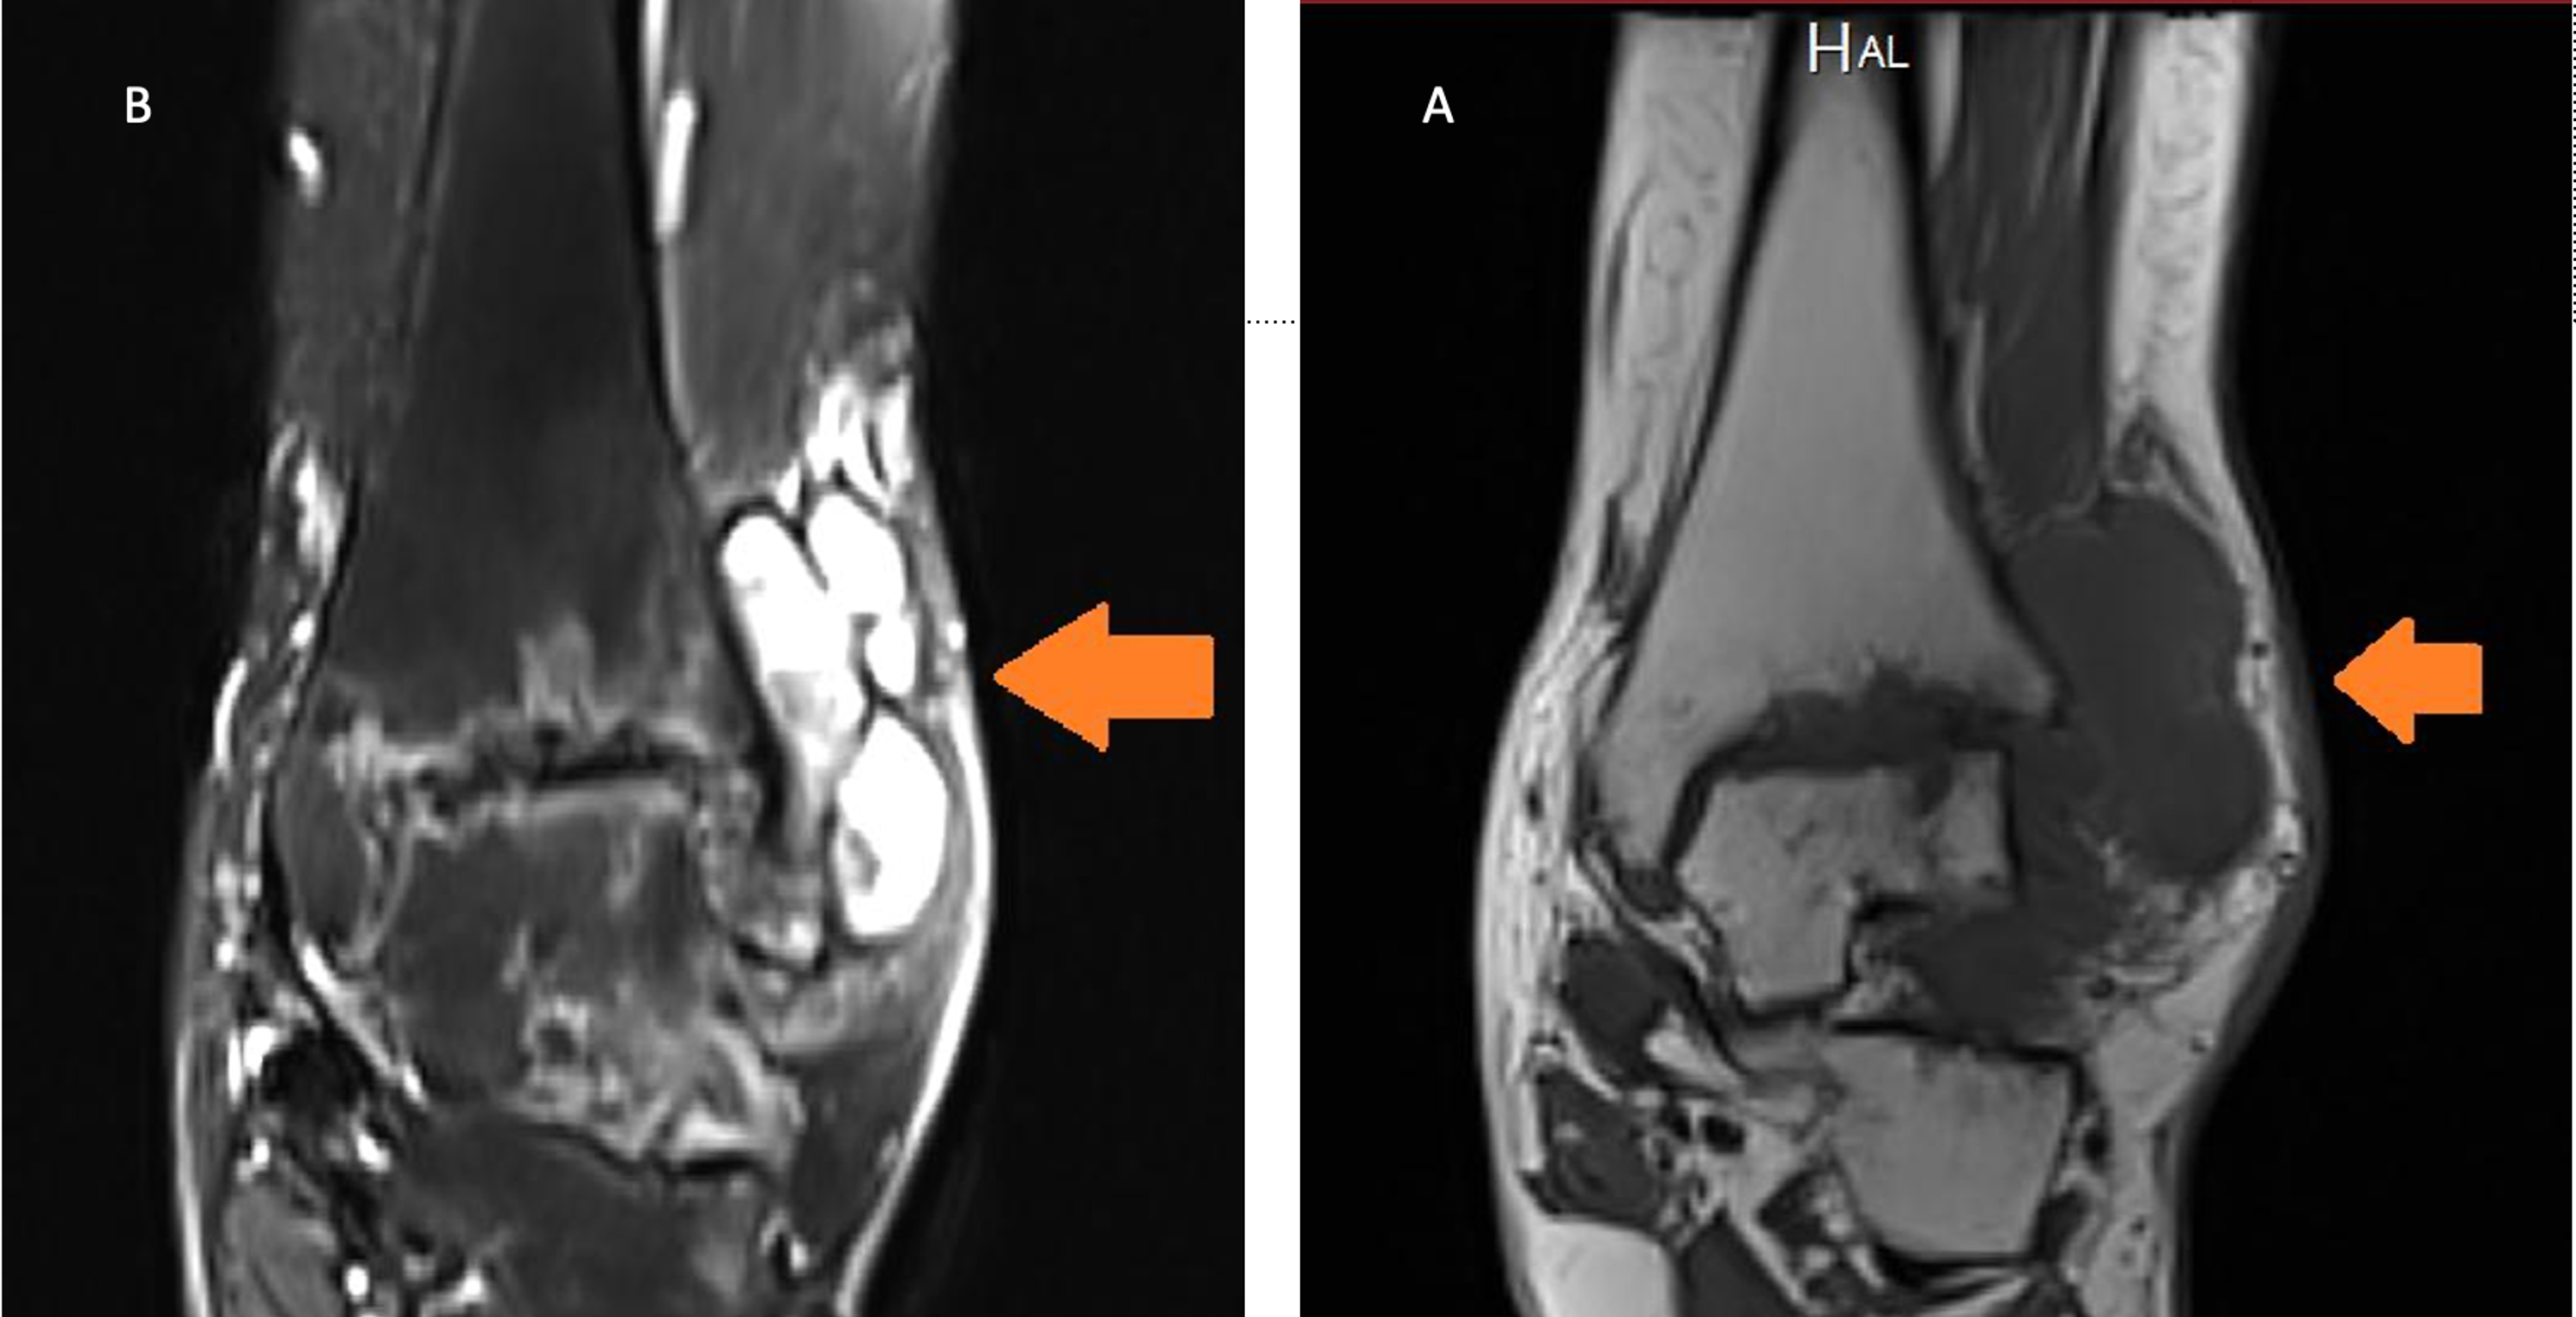

Cureus Tuberculous Arthritis of the Ankle Joint Mimicking Pigmented Arthritis Ankle Radiology to develop a radiographic atlas of osteoarthritis (oa) for use as a template. posttraumatic osteoarthritis (ptoa) of the ankle and hindfoot may be generated by a spectrum of disorders. We use a checklist when evaluating an mri of the ankle: Screen on fatsat images for bone marrow edema. cadaveric, radiologic, and clinical studies have indicated that ankle. Arthritis Ankle Radiology.